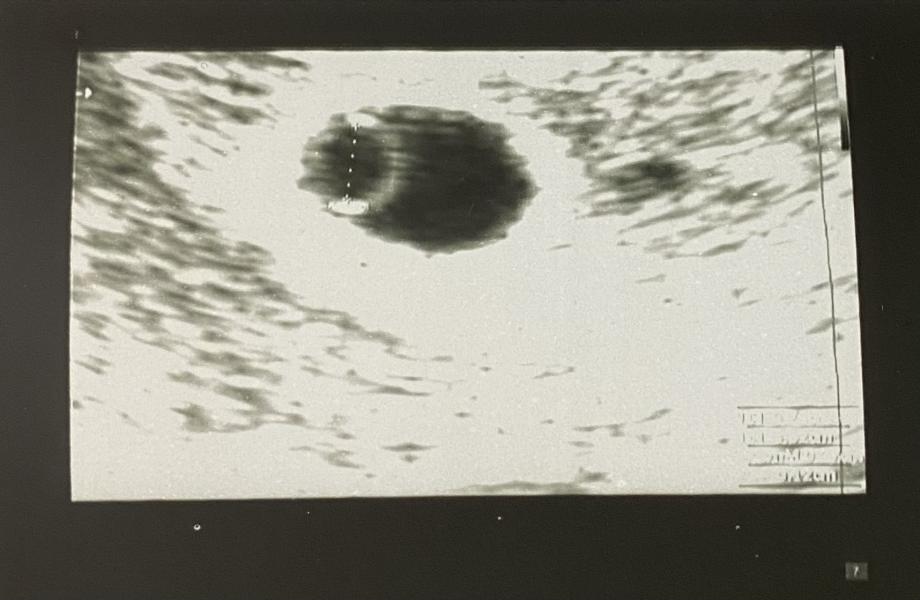

История одной фолликулярной кисты

Планировать беременность мы с мужем начали с декабря 21го года. Я подошла к этому ответственно и сдала все анализы перед планированием) все было в норме, и меня со спокойной душой отправили «работать» над этим вопросом)

Но три цикла прошли вхолостую, беременность не наступала🤔 Я постепенно начала по этому поводу слегка загоняться, хотя знала, что если в течение года Б не наступает, это норма. Но все же я решила, что спокойно ждать год я не смогу, лучше перебдет...

Часть 2